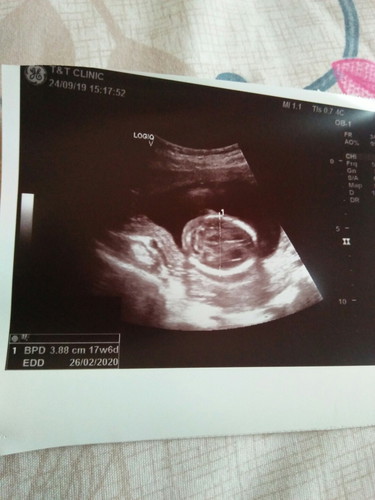

16w6d

Alhamdulillah dpt gak scan baby tdi.. Dr ckp.. Jantung ok.. Baby aktif.. Tulang blkng pun ok. Air ketuban ckup.. Uri pun ok.. Gender... Dr kte baby girl. Tp nanti nk. Scan 20w ke ats.. Nk cnfirmkn gender. Alhamdulillah.. Asalkn baby sihat.. Doakan.. Nanti suami sye blik bulan 11 nk ajak scan baby.. Excited.